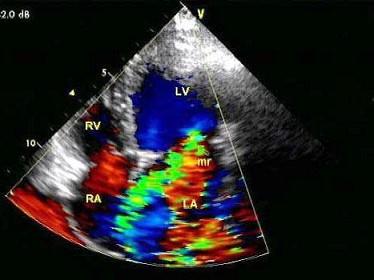

问题 某患者收缩期超声心动图所示,提示?(?)

选项 A.二尖瓣狭窄 B.二尖瓣关闭不全 C.房间隔缺损 D.动脉导管未闭 E.以上都不是

答案 B